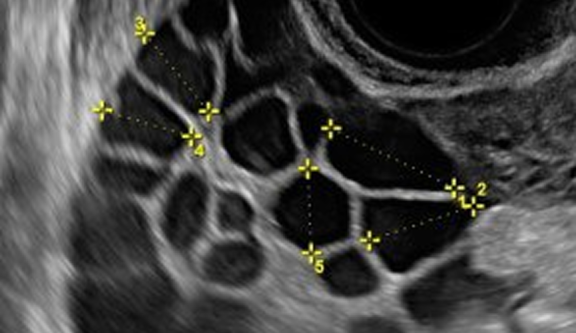

Визуализация фолликулов на УЗИ проводится двумя методами: трансвагинальным или трансабдоминальным. Первый вариант предпочтительнее, поскольку при введении датчика во влагалище удается более детально осмотреть состояние яичников и обнаружить развивающиеся фолликулы. При наличии противопоказаний к трансвагинальному введению датчика выполняется УЗИ через переднюю брюшную стенку.

Фолликулометрия включает несколько УЗИ в одном цикле, чтобы врач мог наблюдать за стадийностью развития фолликула.